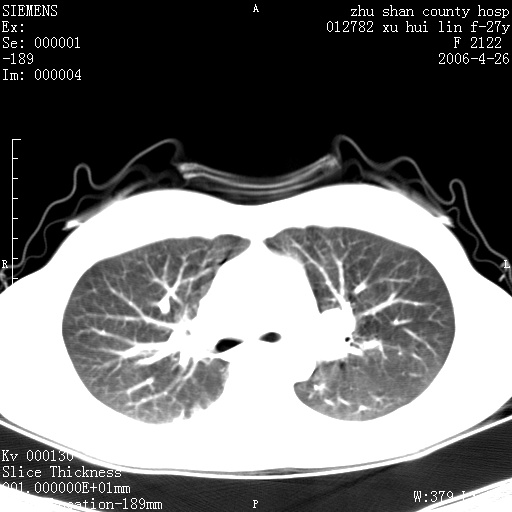

女性 病人 27岁!本院职工家属,五月前因感冒透视发现病变,ct示:左肺下叶背段感染性病变。经过半月规范抗生素治疗后复查病变无明显变化,后行四月规范抗痨治疗,复查无明显变化,后复查无效!请大家帮忙看看!

右肺下叶背段气管狭窄,片状阴影,密度不均,考虑支气管内膜结核可能性大。

右肺下叶背段见片状高密度区,边界不清,密度不均,无钙化及空洞影,背段支气管通畅。所见层面肺门及纵隔内未见明显肿大淋巴结影。

诊断:首先还是考虑为慢性炎症。

结核虽然好发于下叶背段,但周围无明显卫星灶,化验结果怎样?

机化性肺炎

从战友提供的ct图象及定位图象看应该是间质性炎症改变.如果患者不放心可建议她行纤支镜检查.

病人是什么工种,从ct表现看是肺特异纤维化。

局灶机化性肺炎可能,建议她行纤支镜检查